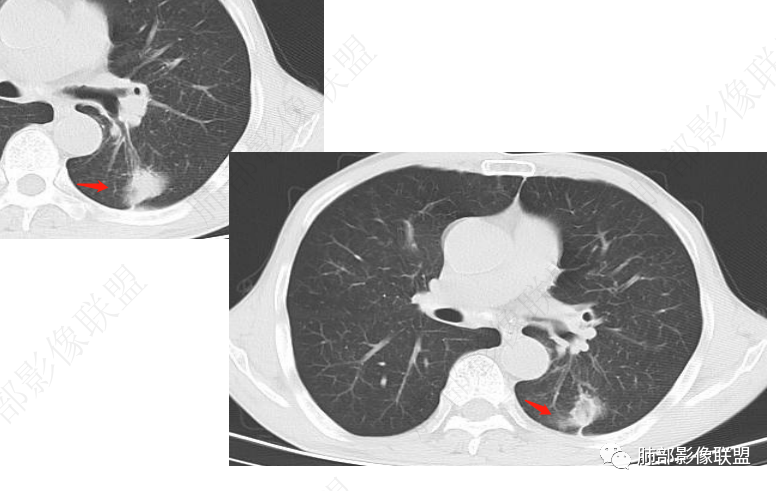

左肺及右肺中叶可见多发斑片状,条索及结节状高密度影,界不清,树芽征(+),中叶伴有支气管扩张,左肺下叶背段结节,周围伴毛刺,近端气管截断,实质密度不均匀,强化方式(看不清),8L,7及4区及左肺门见多发肿大淋巴结,老年男性,感染指标升高,呼吸道慢性病史,二元论,结核+左肺下叶背段恶性结节(鳞癌?)左肺下叶后基底段有新发感染?

左侧胸廓缩小,肺野透亮度较对侧升高,多发微小结节影,下肺结节有刀切征,周围卫星灶,长索条,胸膜增厚牵拉,周边强化,考虑结核,鉴别腺癌。

肺部联盟病例男性67岁,咳嗽咳痰两年加重10天。左肺大结节病灶,边缘有切面,以胸膜下粘连,边界柔软,代表良性的病变。病灶的内部有反晕,边缘有少许的抹玻璃样改变,近端有支气管的半进入,周围有支气管的播散病灶。考虑良性病变,结核的可能性大,鉴别诊断就是隐球菌感染。

老年男性,慢性咳嗽咳痰2年,加重10 天,左肺下叶实性结节影,边缘收缩平直,支气管进入后截断,周围有树芽征及结节影,周围支气管壁增厚狭窄,右肺中叶斑片影,左肺下叶条索影,考虑肉芽肿性炎,肺结核,NTM,考虑肺结核可能性大。鉴别NTM,炎性假瘤等。

左肺下叶不规则实性结节,无毛刺,支气管进入阻塞,周围树芽,远端长索条,左侧胸膜增厚,左肺门淋巴结略增大,右肺中叶支气管扩张,考虑炎性肉芽肿,结核、NTM,鉴别腺癌

左肺下叶不规则软组织密度影,密度不均,胸膜牵拉,环形强化,周围可见多发结节影,左侧肺体积略缩小,左肺上叶多发结节及条索,考虑结核,鉴别腺癌

左肺下叶不规则实性结节,密度不均,支气管进入阻塞,树芽,长索条,边缘强化,考虑炎性肉芽肿,结核、NTM。

左肺下叶结节,反晕,边缘平直,边界不清,卫星灶,考虑结核

慢性病史,急性起病,炎性标志物升高,左肺胸膜下结块,边界似清非清,可见晕中软毛刺,邻近肺野见斑点状卫星灶,可见近端支气管充气征,引流支气管管壁增厚,结块局部边缘平直,可见反晕征,综和分析考虑炎性肉芽肿性病变,尽管隐球夾膜试验阴性,但影像上还是首选隐球或TB,其次粘液腺癌

3.影像表现双肺可见多发斑片状,条索及结节状高密度影,界不清,树芽征(+),考虑肺结核问题不大。左肺下叶背段结节病灶相对另类,应当警惕结核伴肿瘤,如腺癌。该病灶边缘有刀切征,未见典型分叶毛刺,结合周围有卫星灶,胸膜增厚粘连,可疑反晕,边缘有少许的磨玻璃样改变、较模糊,病灶周围有条索、树芽,相对强化较轻微,一元论考虑肺结核可能性大。腺癌如伴有磨玻璃多为中心实性成分周围为磨玻璃成分,且病灶膨隆为主、可见分叶、毛刺、胸膜凹陷、血管集束,脐凹征等征象,本例有轻微胸膜长线牵拉凹陷但其余肺癌常见恶性征象均不明显,且出现边缘平直等明显指向良性病变的征象。